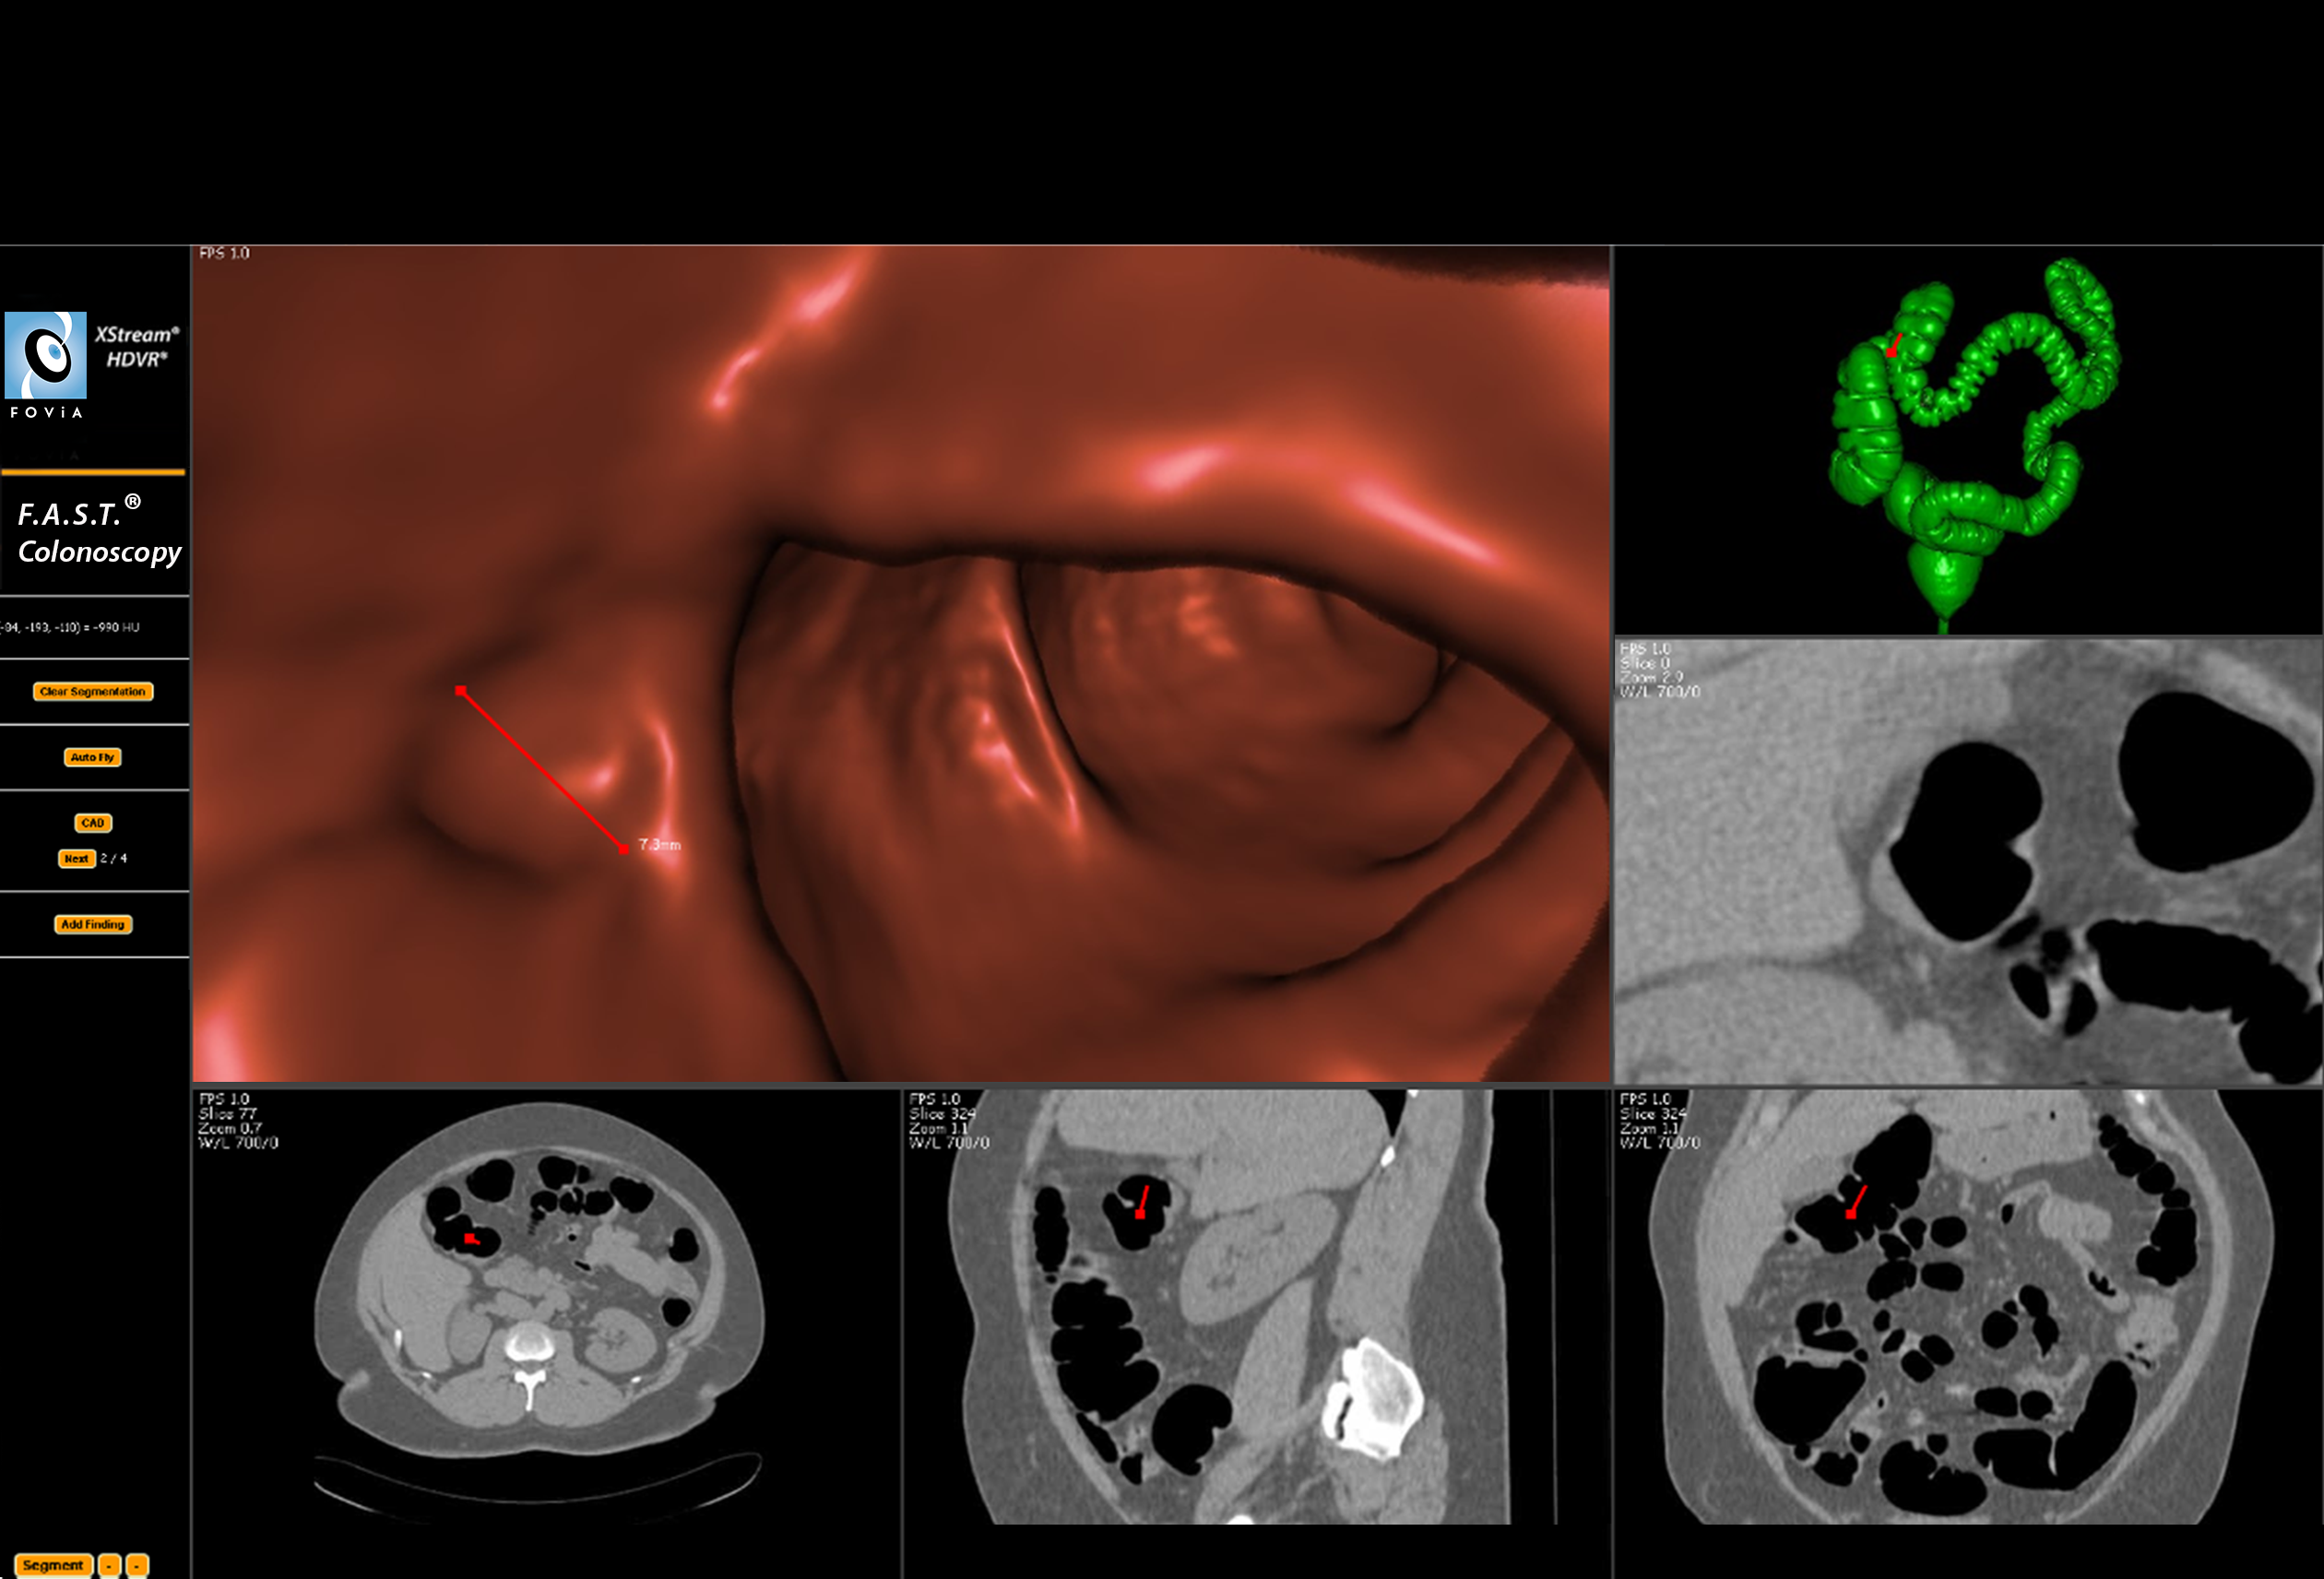

F.A.S.T. Colonoscopy Workflow

F.A.S.T. Colonoscopy Workflow